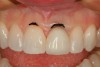

This patient presented with gingival recession above tooth No. 9 (Figure 1). Since this tooth had previous root canal therapy, the exposed root surface was dark and unesthetic. When comparing gingival zenith levels, the maxillary central incisors could be adjusted slightly in the apical direction so that they would be slightly higher than the lateral incisors. Also, the zenith above tooth No. 8 was slightly different in shape (flat) when compared to tooth No. 9. A thin tissue marker (Figure 2) was used to mark the tissue at the proposed corrected level and a photograph was taken to verify positions.

Figure 1  A retracted preoperative view of tooth Nos. 8 and 9 showing disparate gingival heights and a dark root that is visible apical to the crown margin of tooth No. 9.

Figure 1